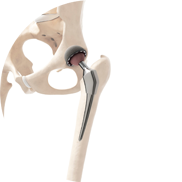

Dr. Vijay Kumar Sohanlal is an esteemed orthopedic surgeon, specializing in joint replacement. Renowned for his expertise in robotic knee replacement , Total knee & hip replacement , revision knee & revision hip replacement, he has helped numerous patients regain mobility and improve their quality of life. He has trained extensively under some of the world’s leading orthopaedic specialists across Australia, Germany, and Mumbai. Dr. Sohanlal’s skills enable him to perform bilateral knee joint replacements in a single sitting, minimizing recovery time and hospital stays for his patients.